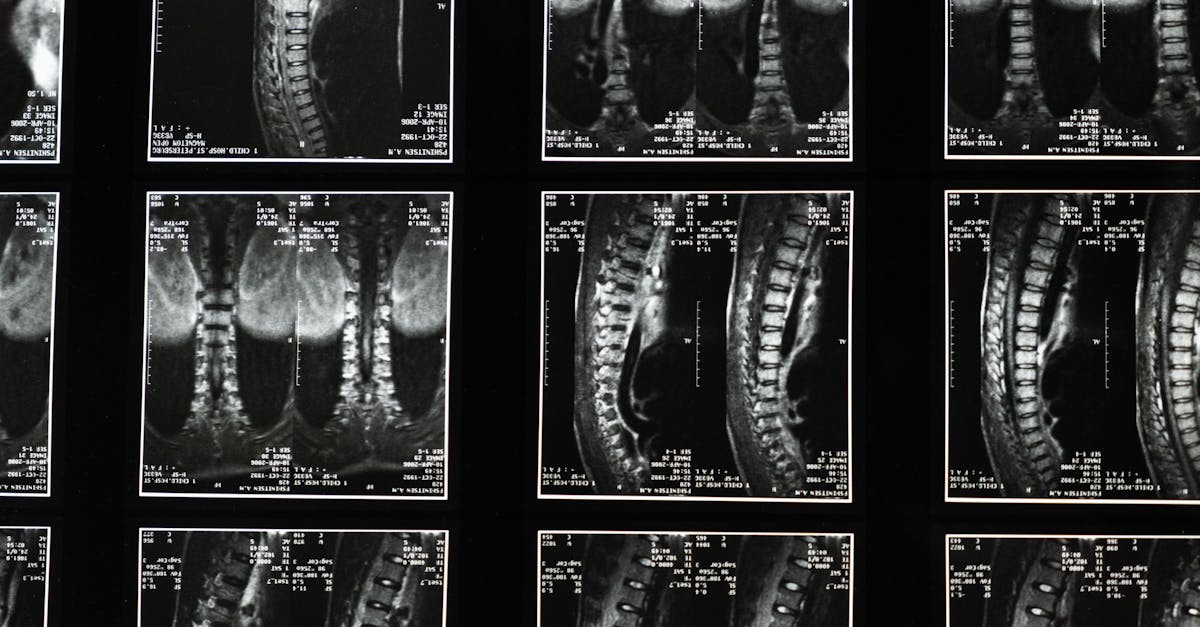

Avant d’entamer un traitement de décompression neurovertébrale, il est crucial de réaliser une évaluation médicale approfondie. Cette consultation permettra de déterminer la cause des douleurs cervicales et d’établir si cette méthode est appropriée. Une analyse détaillée de l’historique médical, des symptômes et des examens tels que l’IRM ou la radiographie doivent être pris en compte pour personnaliser le traitement.

La pratique de la décompression neurovertébrale se déroule généralement à l’aide d’appareils spécialisés, tels que la table de décompression neurovertébrale SpineMED®. Ce traitement doux et non invasif concentre son action sur les zones où les disques intervertébraux subissent une compression excessive. En étirant la colonne vertébrale, ce processus améliore la circulation sanguine et favorise la régénération des tissus vertébraux, permettant aux patients de retrouver une meilleure mobilité et une réduction des douleurs.